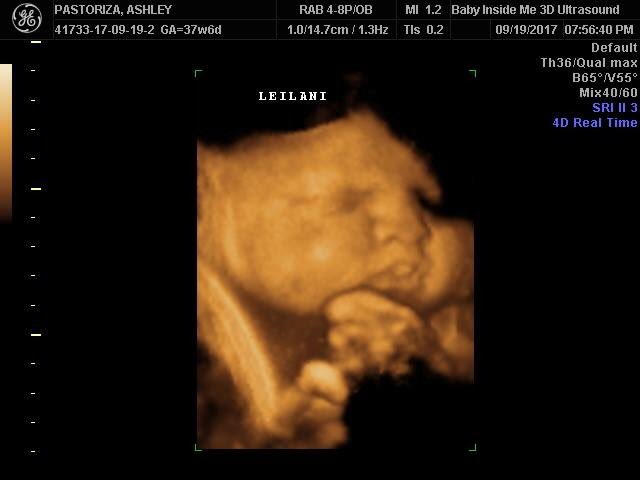

3d ultrasound 37 weeks. I have a doctors appt on the 7th ill be 37 weeks and 1 day pregnant. The purpose is just to make sure my son is head down. While it was amazing to see my son the tech was very inexpirenced and nobody told me at 35 weeks the baby is too big to get a great picture. At this stage the baby has put on some weight and filled out to make features more visible yet still enough fluid in front of babys face to obtain great images.

Has anyone had an ultrasound around 37 weeks and the babys pic looked deformed. 3d ultra sound 37 weeks severelawless. Is that common for ultrasound pics. What it would look like now that youre 37 weeks pregnant your baby is full term.

Vaginal discharge or spotting. So i had my 3d ultrasound done around at 28 weeks and didnt get one good picture. However we do recommend a gestational age of 26 34 weeks for the best facial detail. 3d 5d ultrasound images and 4d ultrasound video can be obtained at any stage.

February 2011 in 3rd trimester. You might notice an increase in vaginal dischargeif you see some bloody show mucus tinged with a tiny amount of blood in the toilet or in your undies labor is probably a few days away. Medical pregnancy scans ivf fertility scans 7834 views. It says 4d real time on the pic but was done at the local hospital just to be checked for fetal growth not a 4d ultrasound i paid for.

Pregnancy symptoms during week 37. 3d ultrasound at 37 weeks. But now im really regretting that i didnt go backdo you think its too late now. A 37 week ultrasound might be performed as part of a biophysical profile.

Learn whats going on with your little one at this part of your journey together. I made the mistake of spending 200 on a 3d 4d ultrasound. Will i still be able to get a good look at him or will he look like the.